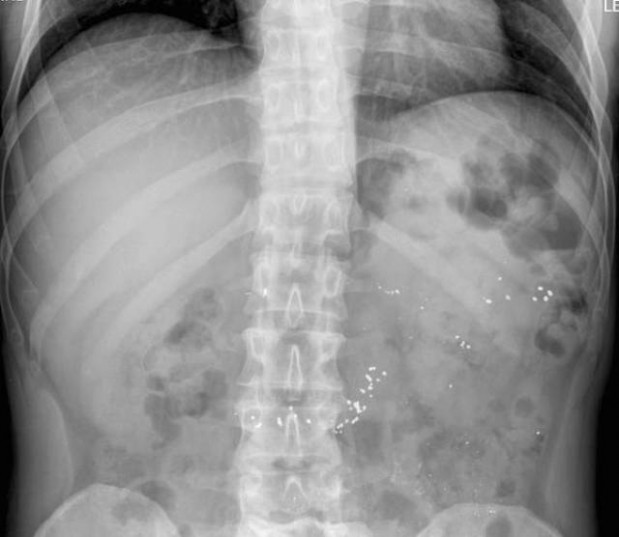

#11 Lämpömittarin hajotessa päälle roiskunutta elohopeaa